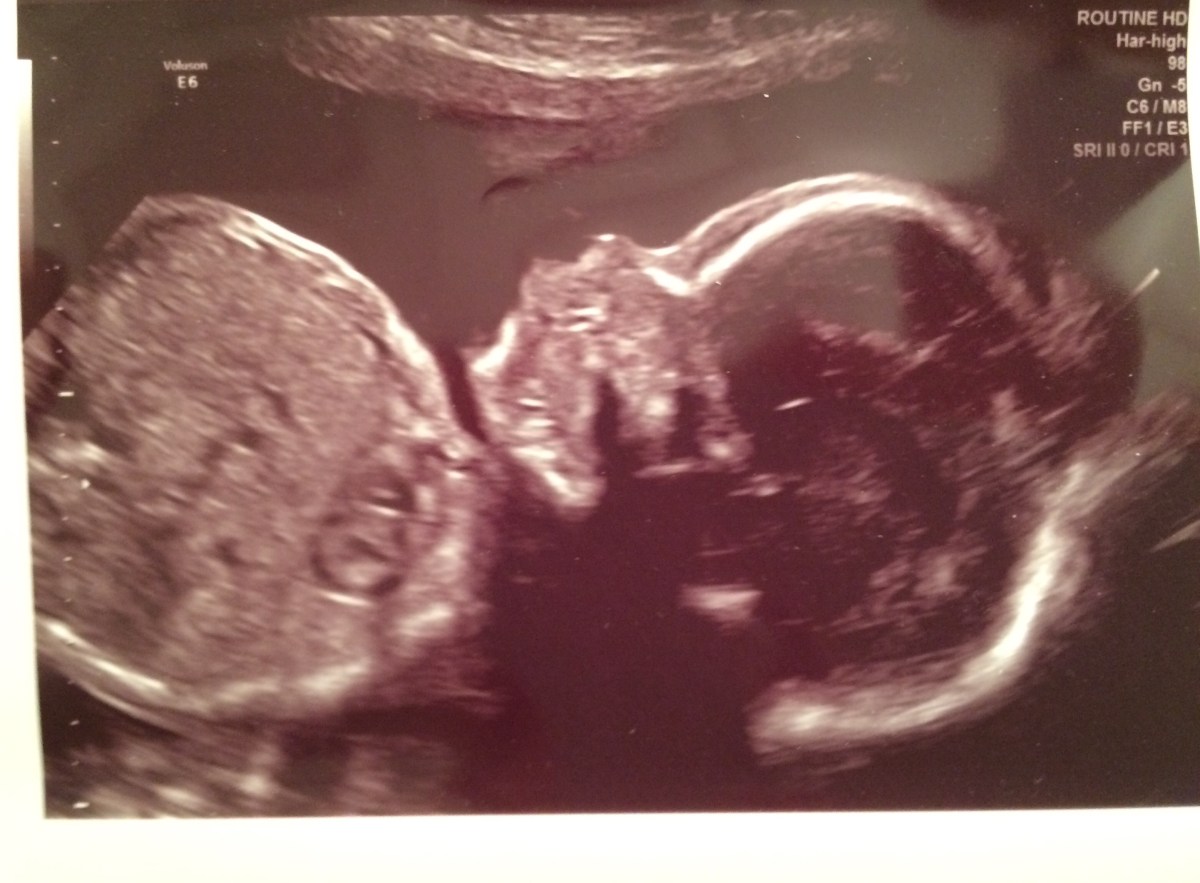

Oh Clark-man, we get to meet you this week. I am as nervous as a long-tailed cat in room full of rocking chairs. I’m scared of meeting you at the same time that I’m really excited to meet you. You are so loved already and your mama has been nuts over getting things ready for you. You are getting here a little earlier than anticipated, but that’s wonderful too. You’ll be here in time for all the Chrismukkah festivities, and we are happy we get to hold you sooner. I pray that you’ll be healthy and avoid the NICU. I pray that you will be strong for whatever days lay ahead. I pray that you’ll be forgiving of the eye-poking big sister you are blessed with. And mostly, I pray for grace as Ben and I enter this new phase of having child(ren) in our lives. We will update once baby Clark gets here. Love to all.